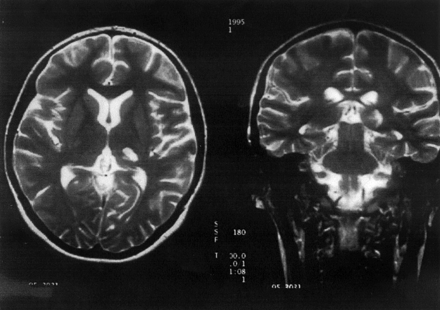

{#/pub/images/mribrainscanLymediseaseandMS.gif}

I have a question.....If there is no cure, and we don't know what causes MS, how do we give MS to mice to study? I was diagnosed in January of 2000. I had actually had the disease, since 1991 or 1992. I went to my family physician, numerous times, complaining of numbness and tingling in various places of my body. I think he thought I was crazy. After having a migraine that lasted 11 days, in 2000, I was given an MRI, which found the MS. I see a great Neurologist from IU in Indianapolis. I pray for a cure. Living with this terrible disease, is for the birds. Thanks for your time.

Can I get an opinion about a spinal tap please. My MRI of my brain clearly shows MS - No dounbt in my MD or Neurologist's minds. But they keep telling me in order to give me medication - I have to get a spinal tap. Any suggestions?

Melissa posted on: August 2, 2012

You mention that your brain MRI definitely shows MS, but in order to have a clear diagnosis, you also need to have two separate episodes of MS-related symptoms at different times. Most doctors cannot accurately diagnose you with just one occurrence, even if you have lesions on the brain; this was true for me 10 years ago when I was diagnosed. Once I had my second relapse, they were able to definitively diagnose me with MS.

Perhaps this is a similar scenario for you? Have you had one, two, or more episodes of symptoms? If you just had one, perhaps your doctor needs to test your spine to see if there are lesions as well. If so, he probably feels comfortable making the diagnosis. But if you had two separate episodes, then from my research and experience, this should be enough to diagnose you and you can definitely get a second opinion. Just take your MRIs to another nero and share your story with him or her.